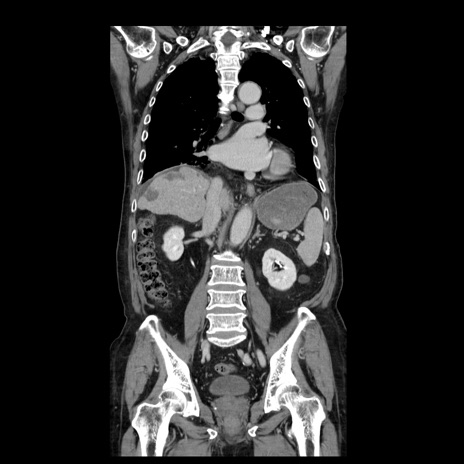

横断像

【症例】70歳代男性

【主訴】腹痛

【現病歴】肝硬変・肝細胞癌にてかかりつけの方。約9時間前に食後より腹痛出現。症状が徐々に増悪し、嘔吐出現したため来院。

【既往歴】肝硬変、肝細胞癌(RFA、TACE後)

【身体所見】意識清明、表情苦悶様、BT 36℃、BP 129/78mmHg、P 88bpm、SpO2 97%(RA)、右上腹部から心窩部にかけて圧痛あり、反跳痛なし、筋性防御あり。

【データ】WBC 5800、CRP 0.16